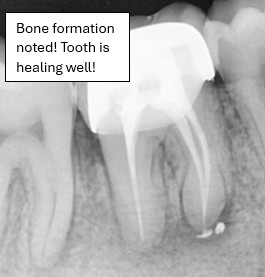

Real Patient Results – Before and After Results of Root Canal Treatment

Discover real root canal treatment results performed by our experienced dental team at Rakyat Dental. These genuine clinical X-rays highlight before-and-after transformations where patients recovered from severe infections and bone loss through advanced endodontic procedures. Each case demonstrates the precision, care, and success of our root canal treatments in preserving natural teeth.